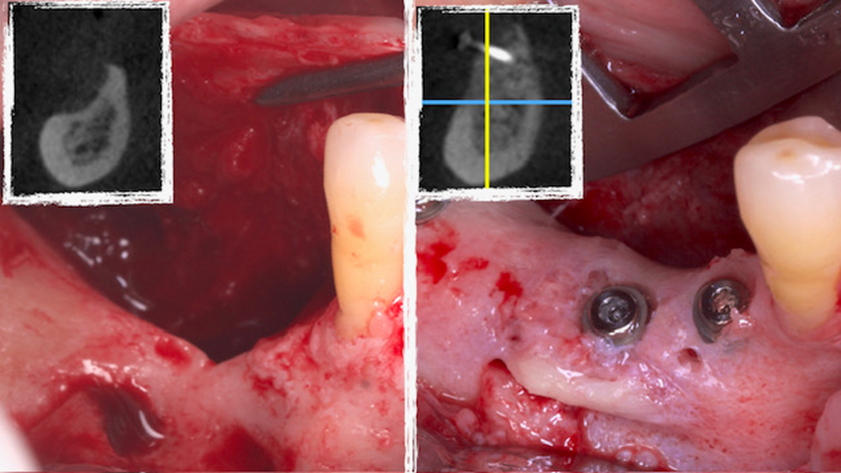

Homem de 60 anos foi encaminhado para reabilitação implantossuportada na região molar inferior direita (Figura 1). O volume ósseo remanescente tridimensional foi acessado por meio de tomografia computadorizada. Revelou uma deficiência vertical de modo que um aumento vertical foi planejado antes da colocação do implante. Seu histórico médico foi verificado e não foram encontradas comorbidades nem condições alérgicas. Não houve achados clínicos intraorais anormais, mas uma deficiência vertical na área molar inferior direita. Nenhum achado anormal foi perceptível no exame extraoral. Um enxerto autógeno em bloco ósseo dividido foi planejado para aumento horizontal e o ramo ipsilateral foi o local doador de escolha. A cirurgia foi realizada sob anestesia local com Articaína 4% e adrenalina 1:100.000. O paciente foi prescrito para enxaguar com Clorexidina 0,12% no pré-operatório, bem como tomar 1mg de Amoxicilina e 8mg de Dexametasona P.O. uma hora antes da cirurgia. Uma incisão mucoperiosteal foi realizada com bisturi número 15C desde o ramo mandibular até a borda mesiovestibular do primeiro pré-molar juntamente com uma incisão perpendicular obliquamente no vestíbulo mandibular. Após o descolamento da mucosa vestibular e liberação do nervo mentoniano, a mucosa lingual também foi descolada (Figura 2). Duas osteotomias verticais e uma horizontal foram realizadas no ramo mandibular com broca 701 para retirada do bloco ósseo necessário à reconstrução horizontal (Figura 3). Após a retirada do enxerto com auxílio de um elevador radicular, o bloco foi cortado longitudinalmente em dois pedaços finos com brocas discais e o osso esponjoso foi raspado para que pudesse ser utilizado como osso lascado (Figuras 4 a 8). Os blocos foram fixados na área edêntula. Um bloco foi fixado na face vestibular e o outro na face lingual. Cada um deles foi fixado com dois parafusos de osteossíntese de 1,5 mm e o osso lascado foi inserido no espaço entre eles (Figuras 9 e 10). A ferida foi fechada com fio de polipropileno 5-0, que foi retirado após 15 dias (Figura 11). A cirurgia cicatrizou sem intercorrências e o paciente recebeu prescrição de amoxicilina 500 mg P.O. a cada oito horas durante sete dias e ibuprofeno 600 mg a cada seis horas durante cinco dias.

Quatro meses depois foram inseridos dois implantes cônicos 3,5 x 9mm (CM Due Cone Implacil De Bortoli) na área enxertada e depois mais seis meses para instalação de coroas provisórias (Figura 12).